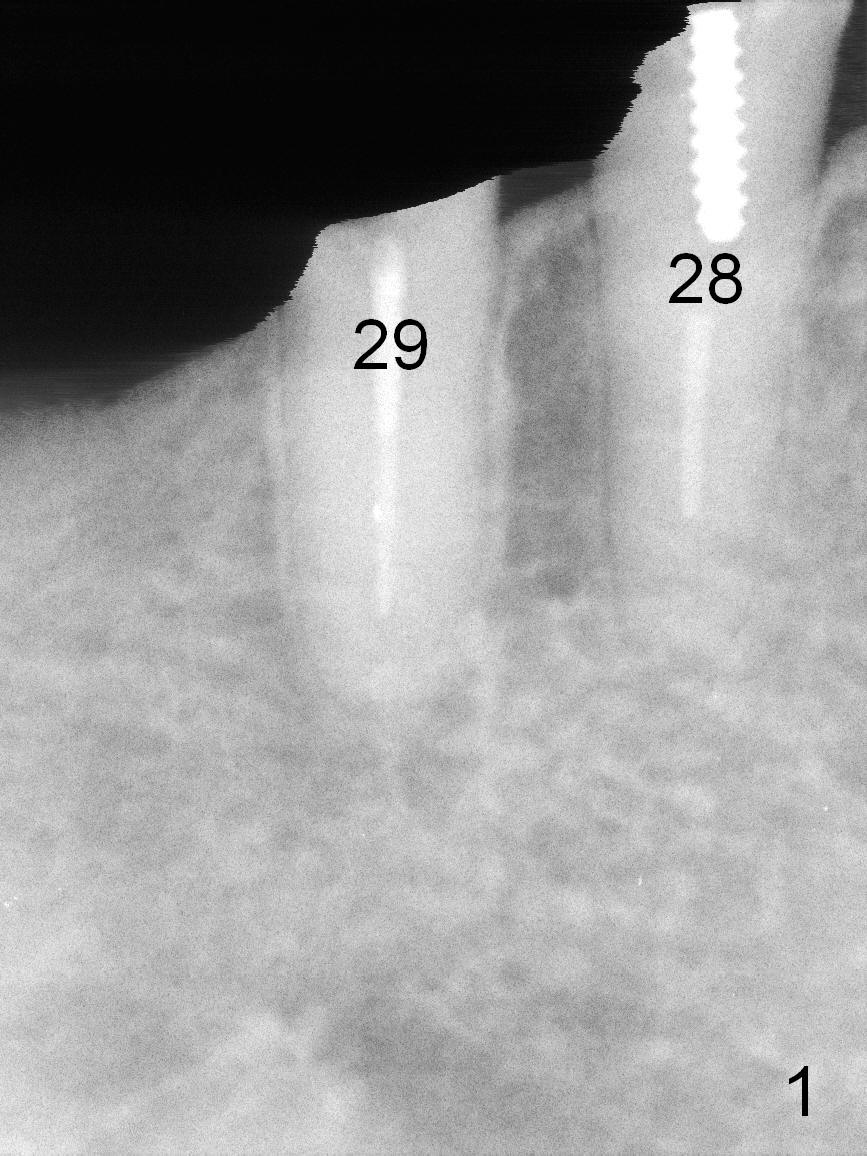

After restoring the implant at the site of #20, the patient returns for #28,29 implant placement (Fig.1,2). Bone level and distance from the Mental Loop (Fig.2 red dashed line) are different. It appears that longer implant can be placed at #28 than that at #29. Parallel pins are placed after initial osteotomy (Fig.3), it appears that the osteotomy at #29 should be moved mesially (arrow). Next PA shows that the position of the osteotomy at #29 is corrected (Fig.4). The position of the implants (4.5x17, 4.5x14 mm) appears ideal (Fig.5). After preparation for an immediate provisional, bone graft is placed in the remaining socket space (Fig.6 *). The splinted provisional is temporarily placed (Fig.7 P). The implant at #29 seems to be buccally placed. After CBCT confirmation, it should be removed for replacement. In addition to moving the osteotomy lingually, there is apparent space (~3 mm) to extend the osteotomy apcially for primary stability (Fig.8 arrow). The apical diameter of the implant is 3 mm.